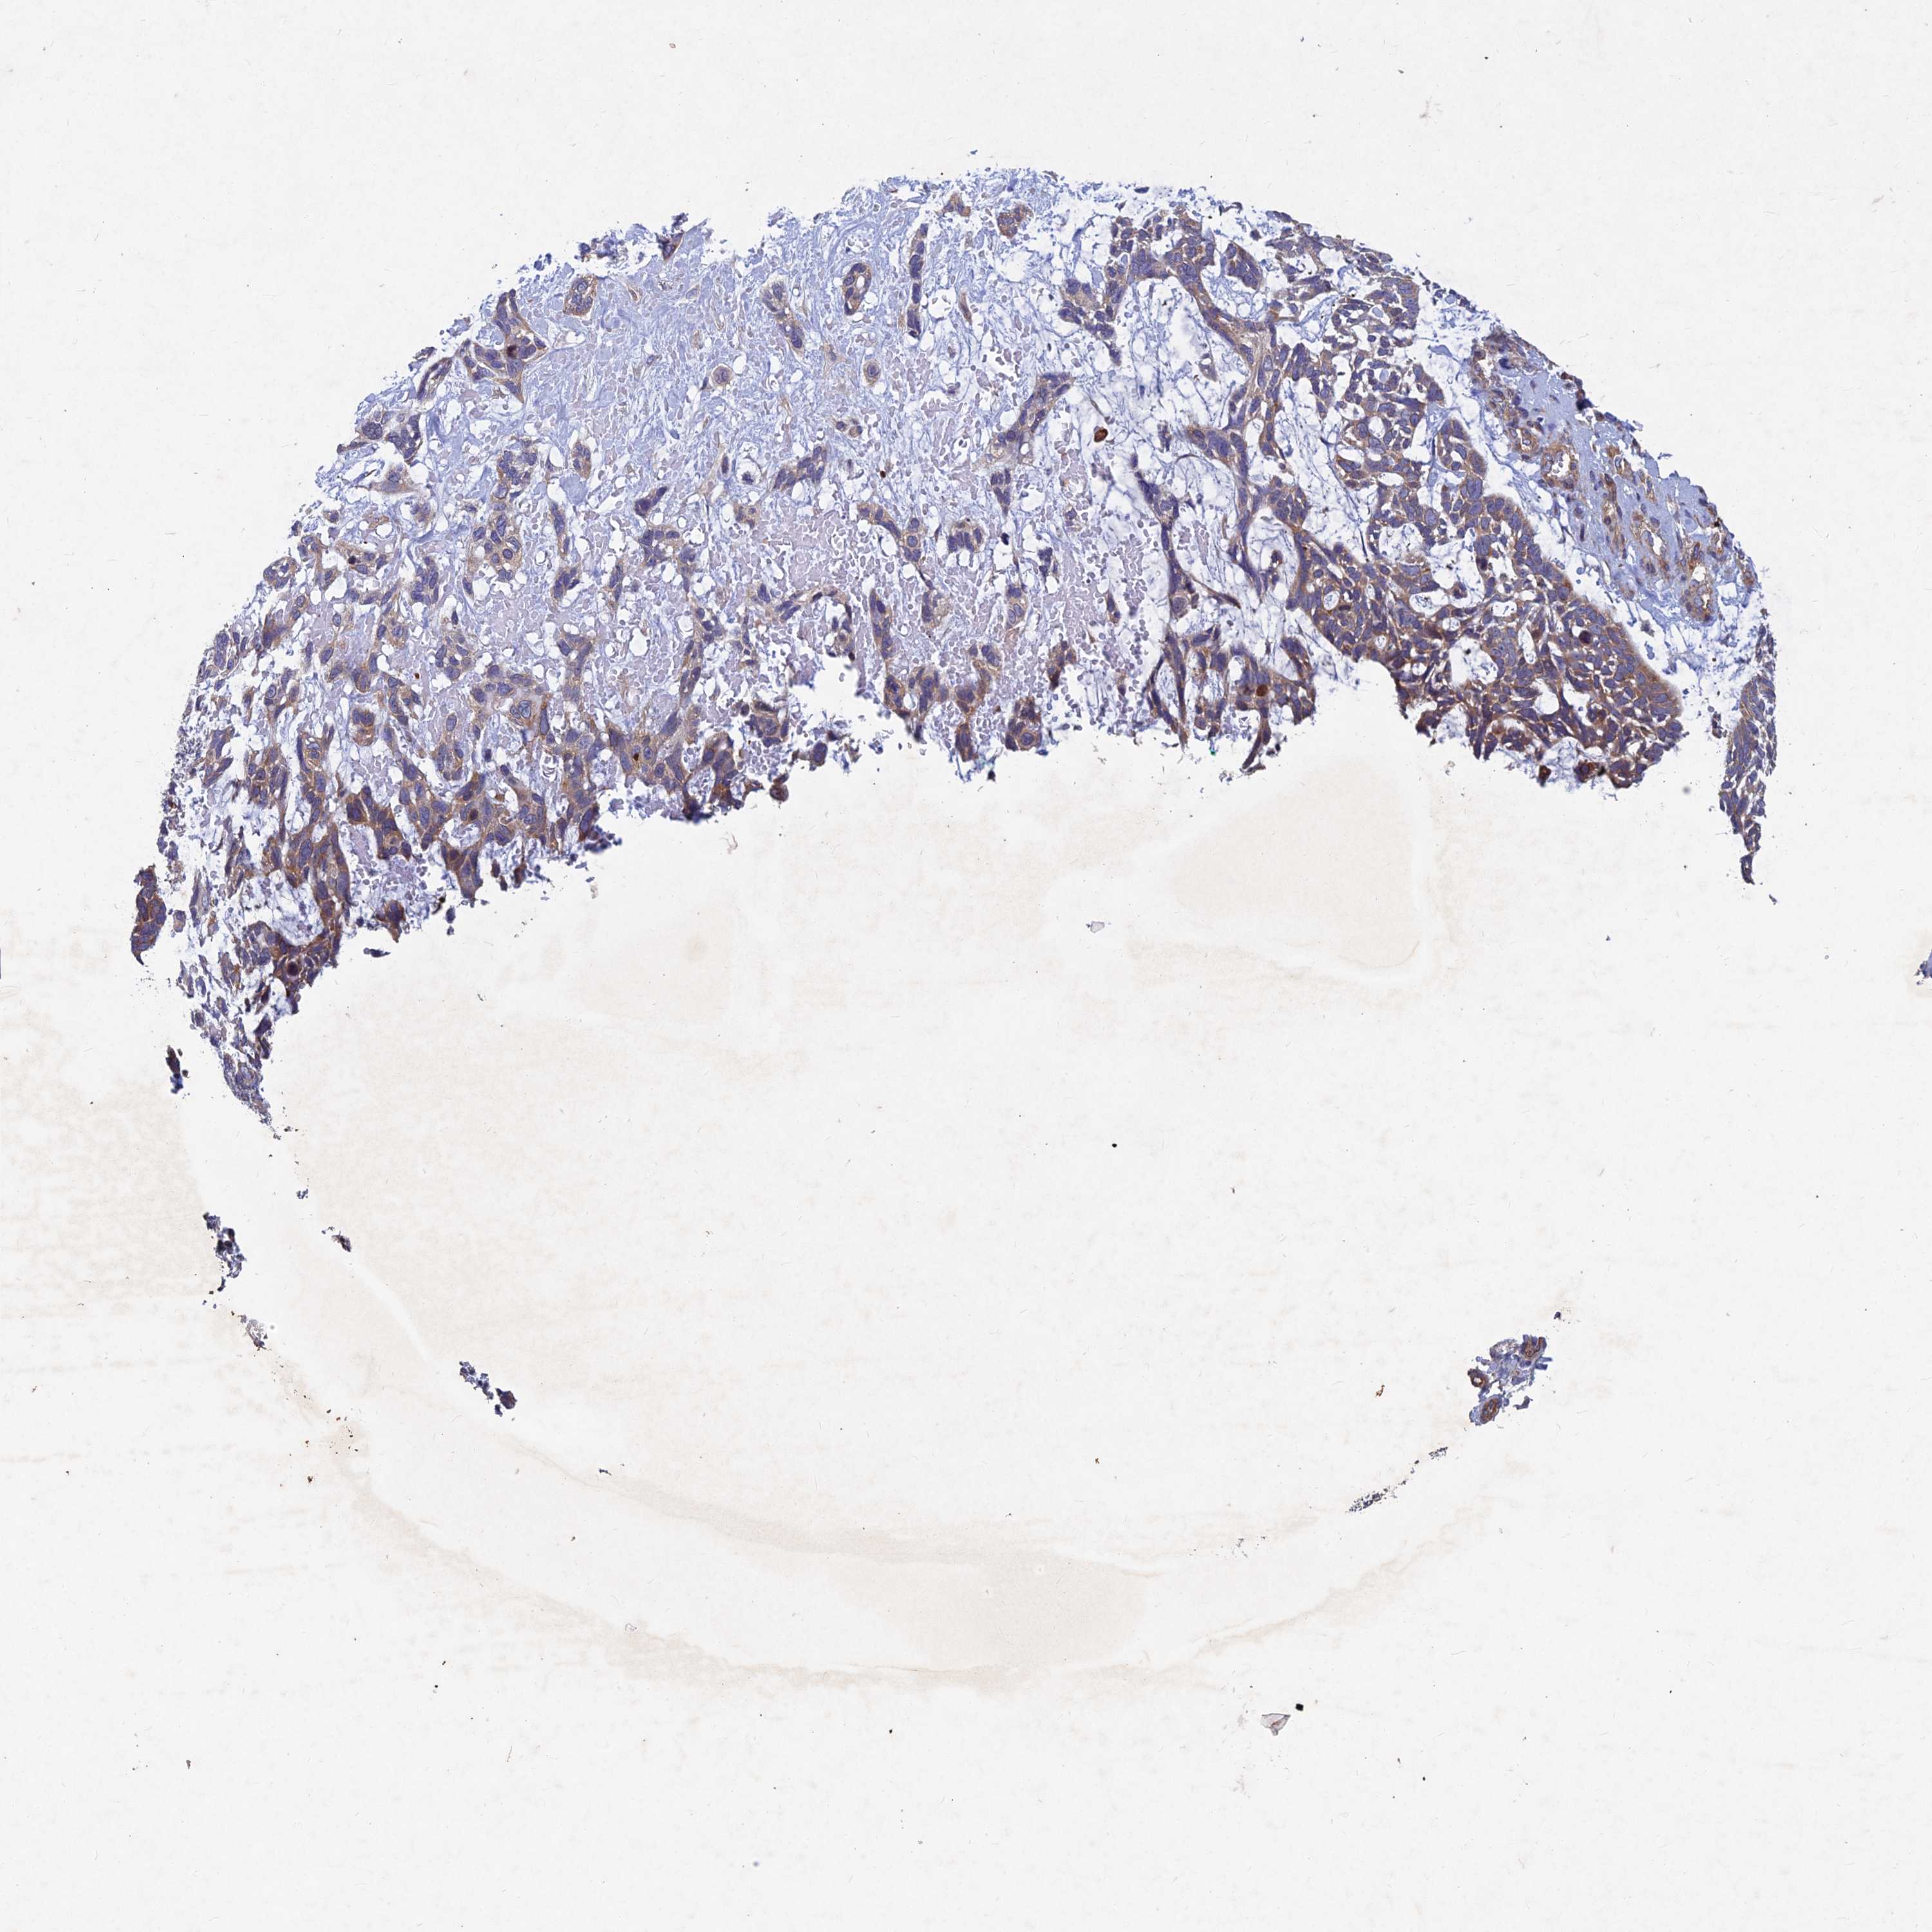

SKIN CANCER - Protein expressioni

A mouse-over function shows sample information and annotation data. Click on an image to view it in a full screen mode. Samples can be filtered based on level of antibody staining by selecting one or several of the following categories: high, medium, low and not detected. The assay and annotation is described here.

Antibody staining in the annotated cell types in the current human tissue is reported as not detected, low, medium, or high, based on conventional immunohistochemistry profiling in selected tissues. This score is based on the combination of the staining intensity and fraction of stained cells.

Each image is clickable and will lead to virtual microscopy that enables deeper exploration of all samples and also displays staining intensity scores, fraction scores and subcellular localization as well as patient and tissue information for each sample.

Antibody HPA039613

Squamous cell carcinoma, NOS

Squamous cell carcinoma, metastatic, NOS